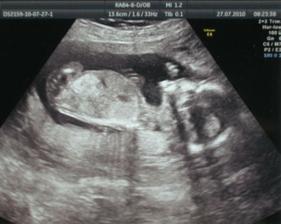

27. července 16+2tt - 2. poradna, krev na triple testy, malé má 160g, já 61kg. Pořád se zdá, že by to mohla být holčička.

17. srpna 19+2tt - 3. poradna, vše OK, akorát mi extra natýkají nohy - proběhnu internou. Malé má 304g, já 63kg (+10kg). Pořád se zdá, že by to mohla být holčička. Během utz kontroly si furt cpala ruku do pusy a vyčůrala se.

24. srpna 20+2tt - trojitý test, velký a 3D utz, vše OK, děvčátko potvrzeno. Ruce pořád nastřídačku v puse, smála se a kopkala o 106.

26.října 29+3tt - 7. poradna, vše OK, kontrola, že to bude opravdu děvčátko, já 67,5kg (+14,5kg).